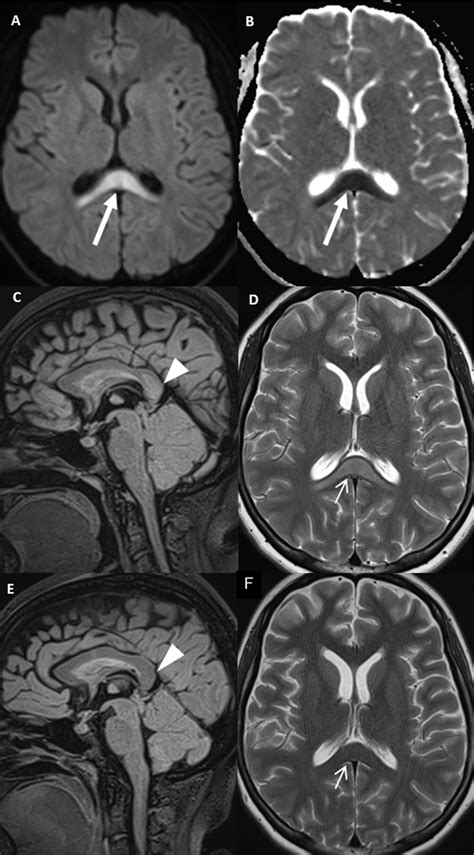

Due to its high concentration of neural pathways, the splenium of corpus callosum is a frequent area of interest in neuroradiology. Magnetic Resonance Imaging (MRI) is the gold standard for evaluating this region. Changes in the integrity of the splenium can be a marker for a variety of neurological conditions, ranging from developmental disorders to acute inflammatory processes.

When clinicians observe signal abnormalities in the splenium, they often look for what is termed "reversible splenial lesion syndrome" (RESLES). This condition often presents with acute onset of symptoms such as confusion, seizures, or vision changes, but interestingly, the lesions often resolve over time without permanent damage. This highlights the unique vulnerability and resiliency of the splenium to metabolic and inflammatory stressors.

Modern neuroscience is increasingly focused on "connectomics"—the comprehensive mapping of neural connections in the brain. The splenium of corpus callosum is a central component in these connectome maps. By using techniques like Diffusion Tensor Imaging (DTI), researchers can visualize the direction and integrity of the fibers within the splenium with unprecedented clarity. This technology allows scientists to see how different brain regions are "wired" together and how these wires change in response to learning, aging, and disease.